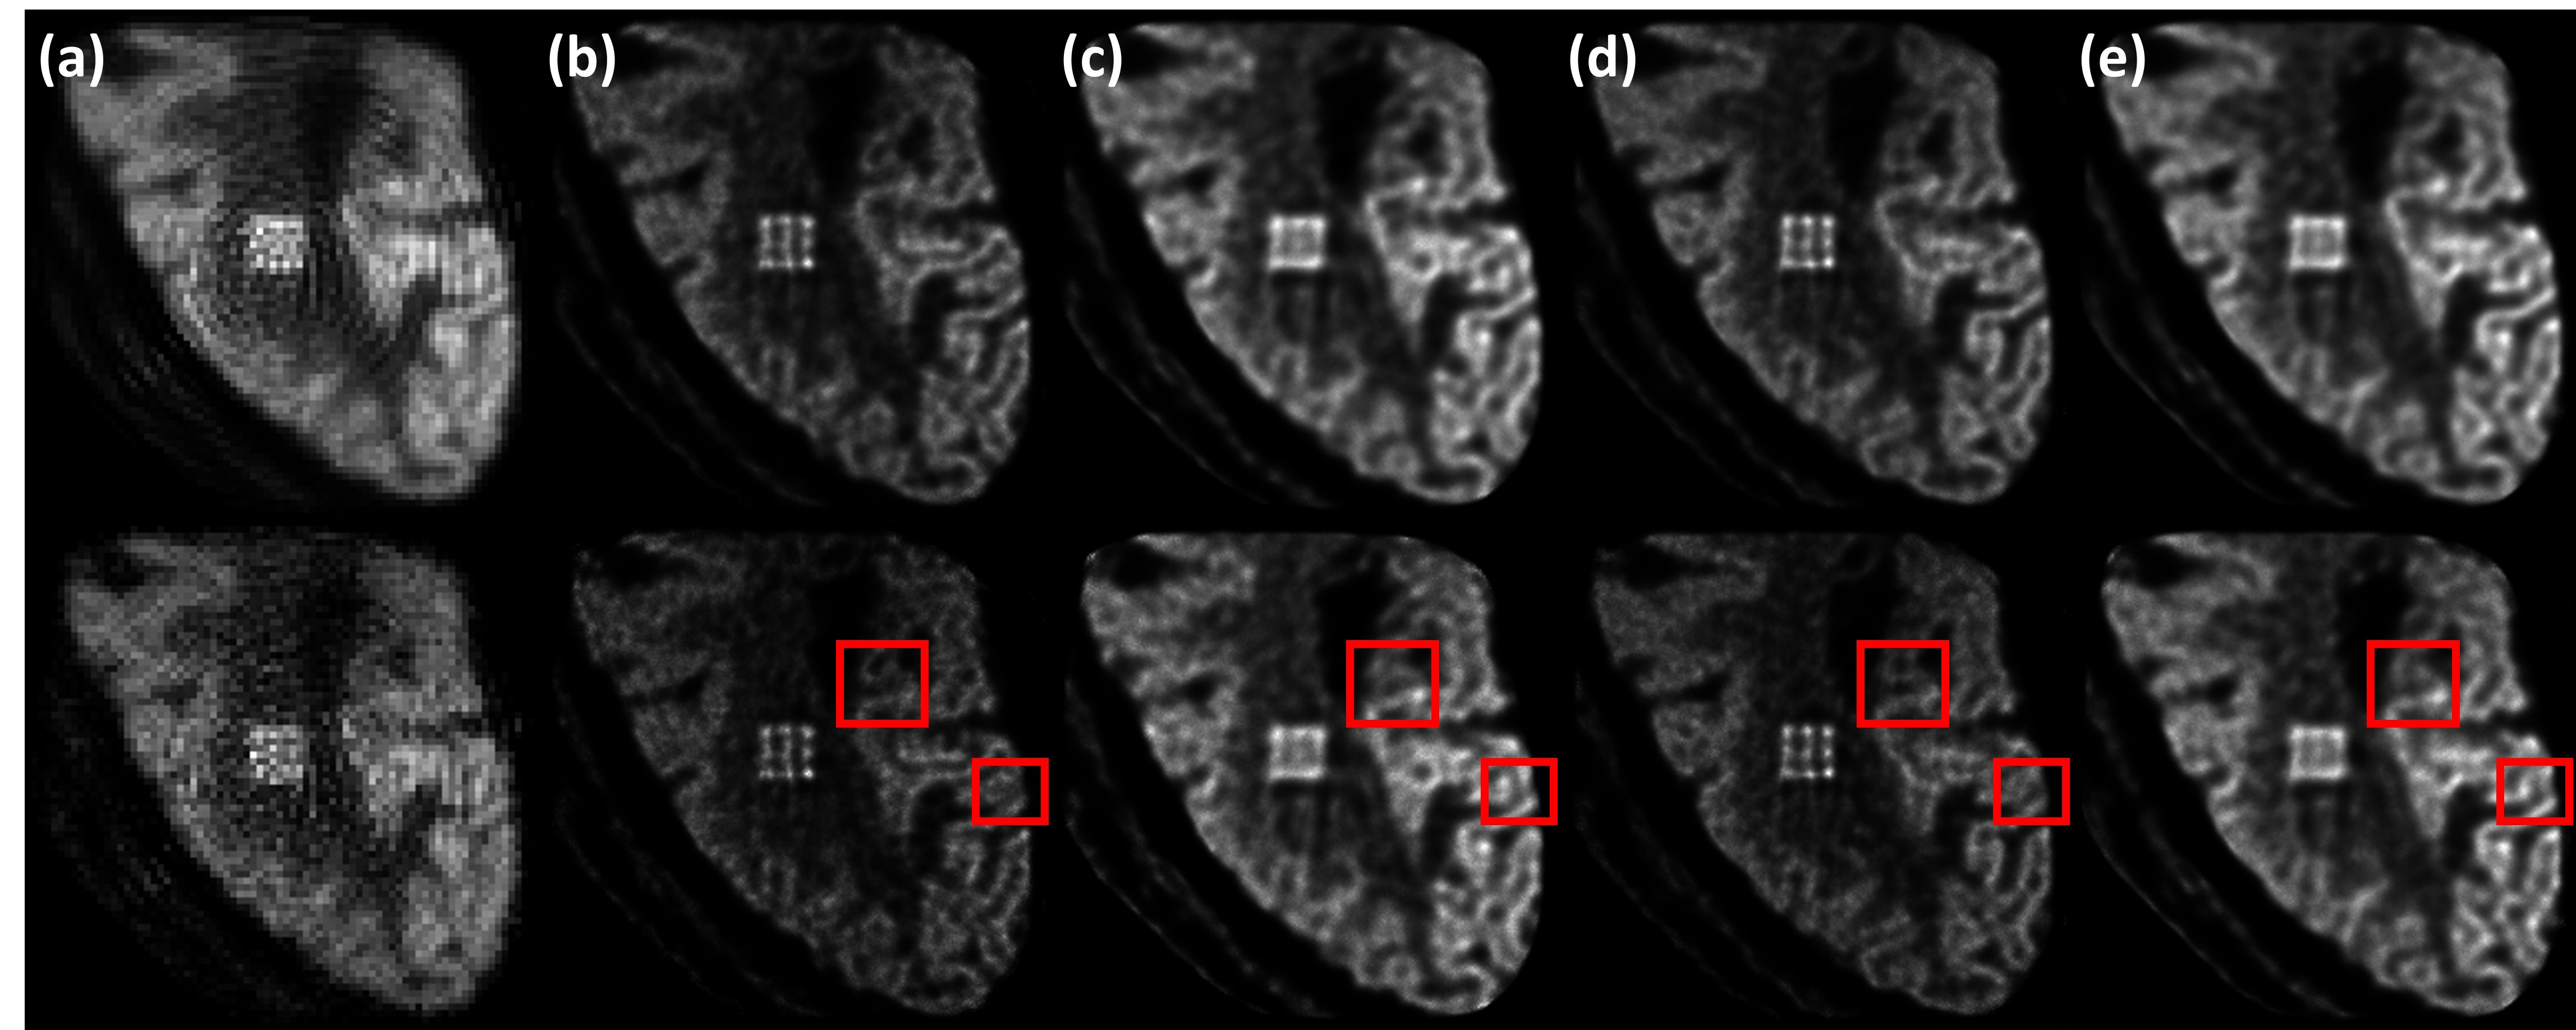

Figure 14: S (a), M2 (b,d), and M0 (c,e) images of the brain phantom obtained from GATE simulation data. Two datasets corresponding to two different scan durations were produced for the situations when no modulator was used (S and M0) and when the M2 modulator was used. The M2 and M0 data in dataset 1 had 7.7M events (b) and 13.2M events (c), respectively. In dataset 2, they had 13.4M events (d) and 23.0M events (e). The S image used the M0 data in dataset 1. Images in the top (bottom) row were obtained using 25 (50) iterations. Compared to the phantom in Fig. 2(b), structural errors in the M0 images can be observed (the red rectangles show two examples).

Fig. 14 shows the S, M0, and M2 images obtained from GATE simulation data of the brain phantom. As in Sect. IV-E, 1.0 mm pixels were used for S and 0.3 mm pixels were used for M0 and M2. Two datasets simulating different scan durations were produced, yielding 7.7M and 13.2M events for M2 and M0 in dataset 1 and 13.4M and 23.0M events for M2 and M0 in dataset 2. Again, it can be observed that the S image has the lowest spatial resolution and also suffers from ring-like artifacts. Under the same scan duration and OSEM iteration number, even though it had only about 43% fewer events, M2 shows considerably better resolution than M0. For both datasets, the lesions are resolved in M2 but not in M0. Visually, M2 can clearly resolve most gyri while the boundaries are less distinct in M0. Some structural errors also appear in M0.